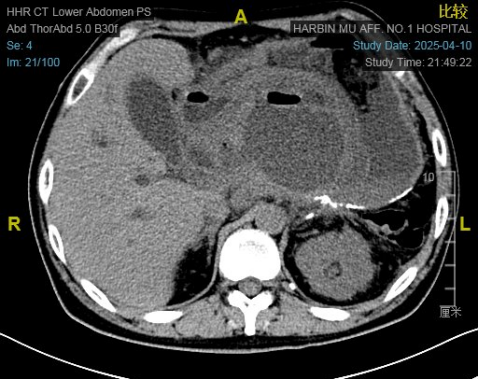

王先生入院CT影像